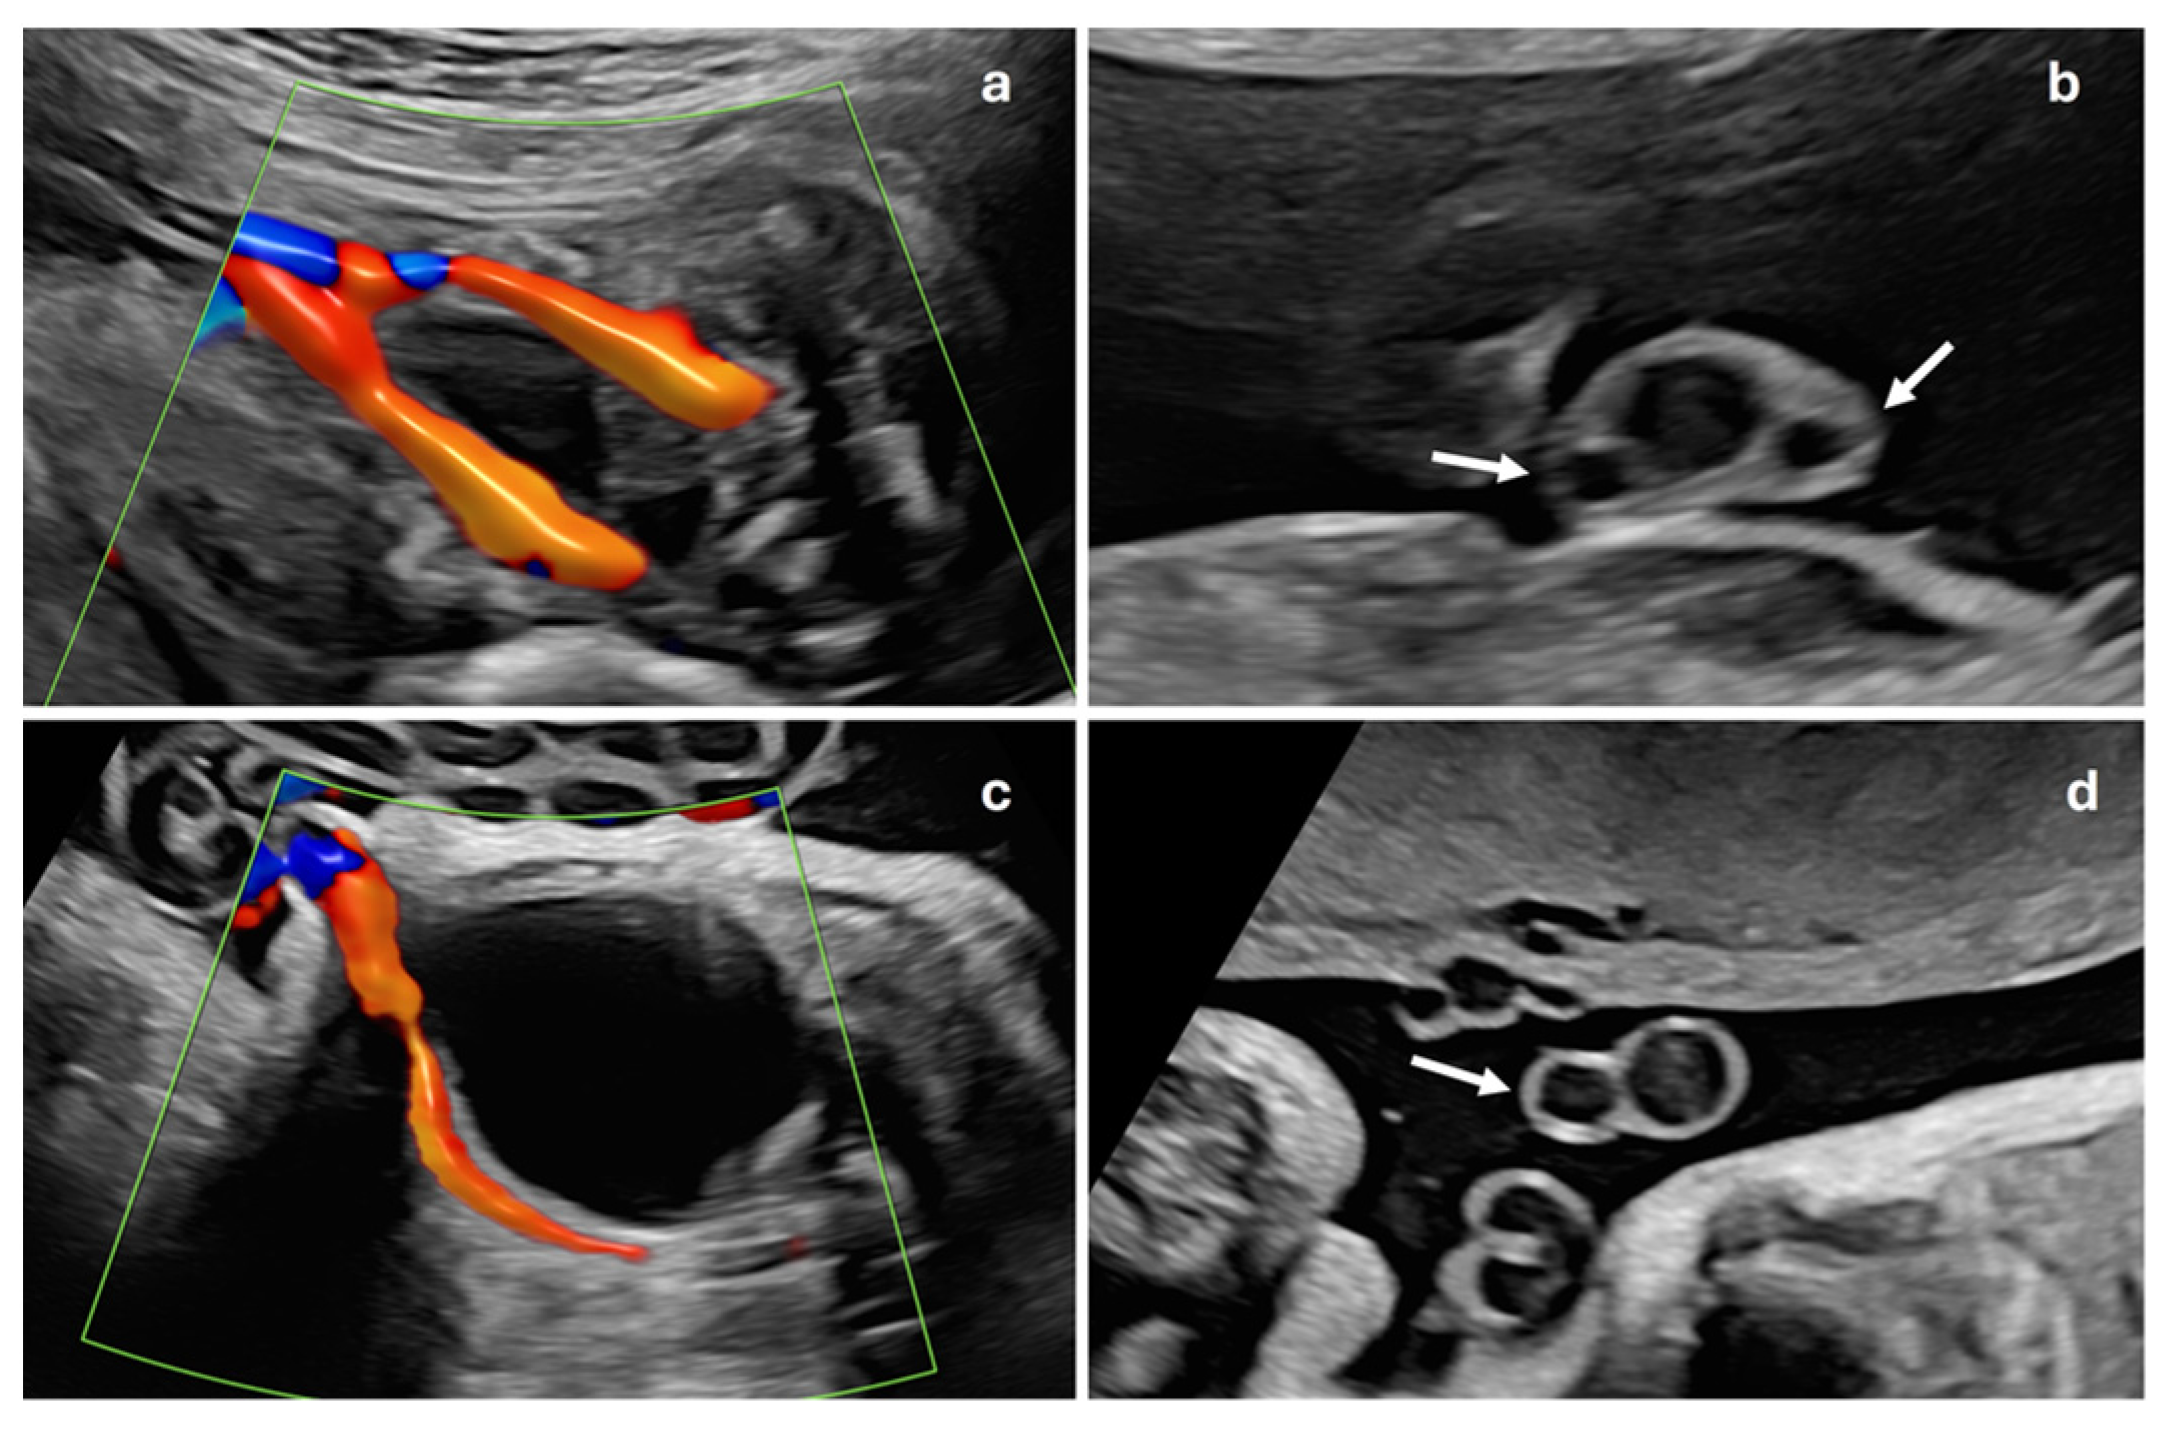

This is a descriptive, observational and retrospective study with a total of 1157 consecutive singleton pregnant patients treated at the Department of Gynaecology and Obstetrics of the Hospital Universitario de Salamanca, during the period from 1 January to 31 August 2023. Inclusion criteria were women with singleton gestations without other associated ultrasound markers, nuchal translucency less than 3.5 mm and no fetal malformations. Exclusion criteria were multiple gestations or those that did not meet the inclusion criteria. These pregnancies were compared with 77 gestations with ISUA, whose data were collected during the years 2019 to 2023 at the same center, ISUA being defined as the presence of a single umbilical artery without any other ultrasound signs or markers or fetal malformations (Figure 2). All ultrasound examinations were performed by one of the five specialists belonging to the Prenatal Diagnosis Department at the 20th-week ultrasound scan (AMC, MOMR, PO, AVY, FJG), following the ISUOG Protocol for the performance of the routine mid-trimester fetal ultrasound scan [11]. Once ISUA was diagnosed, it was confirmed by another of these specialists in the department at a subsequent visit. This study was approved by the Hospital Ethics Committee. Considering that this was a retrospective study, no informed consent was needed from the patients to carry out this study. Sample size was calculated using the WinEpi calculator (http://www.winepi.net/f102.php, accessed on 1 June 2022), considering a prevalence of 1% for ISUA [8] with a confidence level of 95%. Data were collected in a database created specifically for this study with Microsoft Excel (Microsoft Corporation, Redmond, WA, USA), which was accessible from the outpatient clinic, the delivery room and the hospital ward.

Figure 2. A flowchart showing the patient selection process for this study.